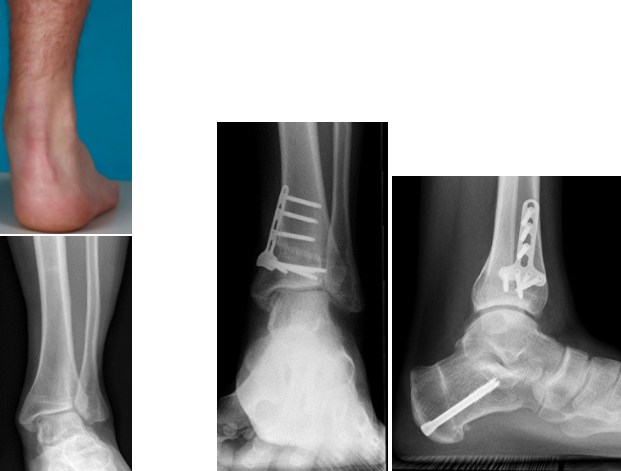

Die supramalleoläre Osteotomie bezeichnet die Achskorrektur sprunggelenksnahe am Unterschenkel. Diese Fehlstellung kann primär entwicklungsbedingt, häufig aber auch im Rahmen von fortgeschrittenen Arthrosefällen oder als Residualzustand nach schweren Sprunggelenksverletzungen auftreten. Am häufigsten handelt es sich dabei um Achsfehler, bei denen der gesamte Fuß entweder nach außen (Valgusfehlstellung) oder nach innen (Varusfehlstellung) gerichtet ist. Folge der Fehlstellung sind der vorzeitige Gelenksverschleiß und die Überlastung von Weichteilstrukturen am Fuß. Seltener besteht ein Drehfehler (Torsionsfehler), der korrigiert werden muss. Eine Spezialindikation stellt eine Achskorrektur der unteren Schienbeingelenksfläche im Rahmen einer fortgeschrittenen Arthrose am oberen Sprunggelenk zur Verbesserung der Fußhebung dar.

Die am häufigsten durchgeführte Technik stellt die zuklappende (ein knöcherner Keil wird entfernt und die zwei Knochenteile werden mittels eines Plattensystems miteinander fix verschraubt) Osteotomie dar. Etwas weniger häufig wird eine aufklappende Osteotomie durchgeführt. Hierbei wird der Schienbeinknochen fast gänzlich durchtrennt und mittels eines „aufklappenden" Manövers wird - über den verbliebenen Knochenanteil als Scharnier – der Osteotomiespalt geöffnet und mittels Knochenspänen aufgefüllt. Zur Stabilisierung wird ebenfalls ein winkelstabiles Plattensystem verwendet.